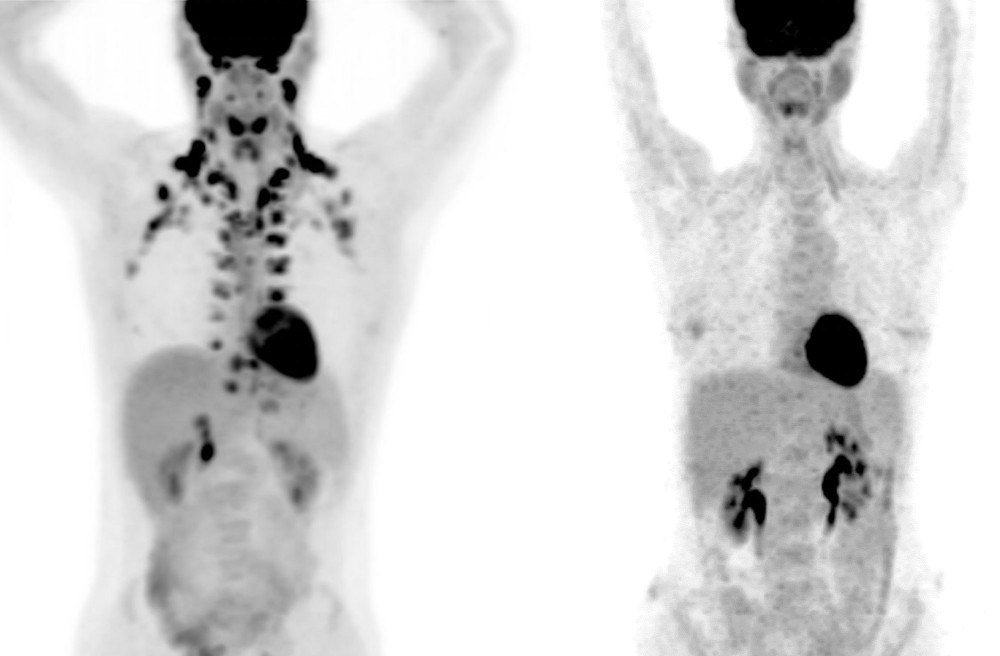

A relevância dos resultados no organismo dos seres humanos também foi testada. Sete voluntários participaram: um deles com câncer e que fazia quimioterapia e os outros seis eram saudáveis. Foram feitas tomografias por emissão de pósitrons (PET) que revelaram uma quantidade significativa de gordura marrom ativada no pescoço, coluna e tórax de adultos saudáveis, que usavam shorts e camisetas enquanto eram expostos a uma temperatura ambiente de 16 °C por até seis horas por dia durante duas semanas.

Já o paciente com câncer usava roupas leves e ficou em uma sala com temperatura de 22°C por uma semana e depois em uma sala com temperatura de 28°C por quatro dias. Assim, os exames de imagem mostraram o aumento da gordura marrom e redução da captação de glicose do tumor durante a temperatura mais baixa em razão da mais alta.